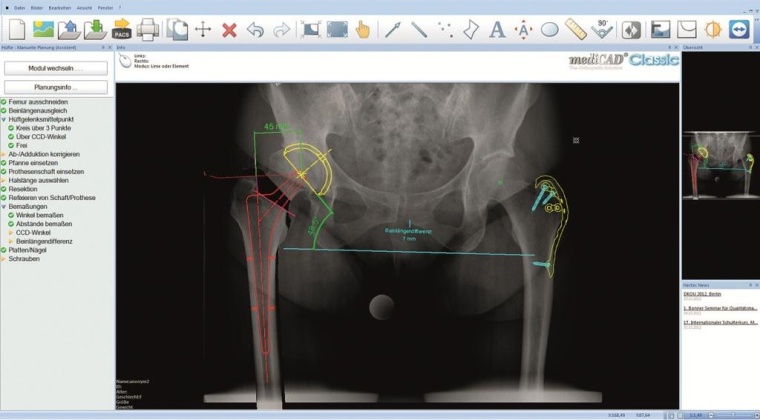

Zusätzlich zur Implementierung des neuen PACS Systems wurde auch die Orthopädie-Planungssoftware „mediCAD" des deutschen Spezialisten hectec (Landshut) klinikweit eingeführt. Bei dieser Anwendung handelt es sich um eine medizinische CAD-Software, mittels derer Implantate und zugehörige Komponenten im PACS über die Radiologiebilder gelegt / geplant werden können. So kann beispielsweise bei einer Hüftoperation eine geeignete Pfannen-/Schaftkombination effizient am System geplant und archiviert werden.

Das Planungsprogramm für orthopädische Chirurgen und Kliniken ist in der aktuellen Version deutlich erweitert und ergonomisch optimiert worden. Automatisierte Abläufe und die effektive Bedienung sparen zusätzlich Zeit. Insgesamt sind über 100 neue Funktionen und Änderungen hinzugekommen. Die hectec GmbH entwickelt ihre Planungslösung „mediCAD Classic" seit 1999. Das Programm ist zertifiziert und weltweit als Medizinprodukt zugelassen. Es berücksichtigt alle Planungsmethodiken und dokumentiert alle Vorgänge gesetzeskonform und rechtssicher. In der Uniklinik Balgrist setzen alle Spezialisten-Teams die Planungslösung ein, z. B. für Schulter- und Hüft-OPs sowie in allen Bereichen der unteren Extremitäten, wie Knie und Sprunggelenk. Über die OP-Planung hinaus ist mediCAD durch seine zahlreichen Möglichkeiten zur Messung ein wichtiges Instrument bei der Diagnostik etwa bei der Wirbelsäule geworden.

Zentral verfügbar ist auch die von mediCAD zur Verfügung gestellte Implantat-Datenbank, aus welcher der Arzt sofort auf dem Bildschirm das optimal passende Implantat auswählen kann. Die Datenbank wird fortlaufend erweitert, umfasst heute die Artikel von weltweit 105 Herstellern und deckt in Europa über 80 Prozent aller verwendeten Implantate ab. Die Lösung passt sich nahtlos in die EDV-Ausstattung der Kliniken ein. Sowohl die Integration in das neue PACS System als auch der Zugriff auf alle Templates haben sich an der Uniklinik in der täglichen Arbeit als besonders vorteilhaft erwiesen.